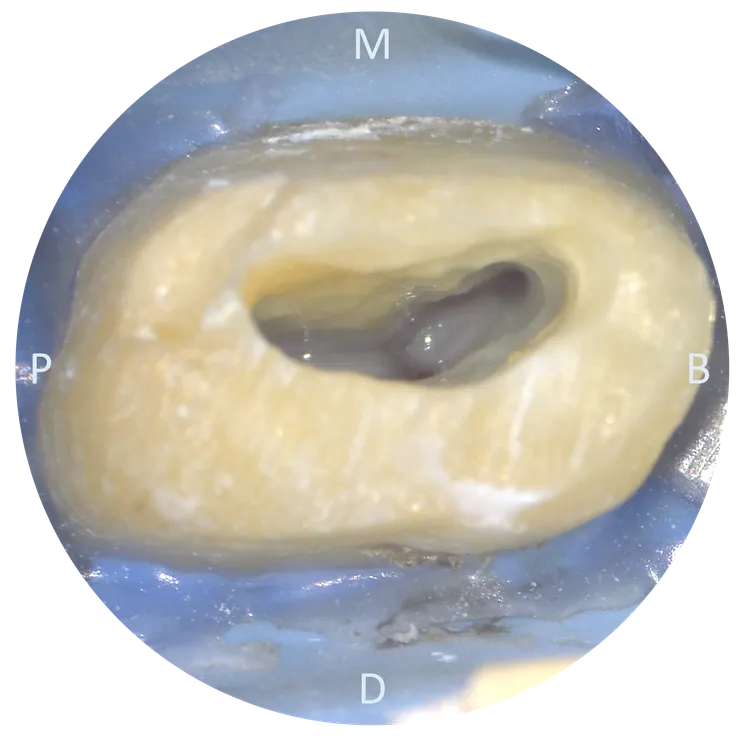

接下來是 #20241224 43 歲的 26.DB orifice 上方也是類似的情況,有一區蓋過來的 dentin. 但因為 DB 洞明顯的比 MB2 洞大多了,所以我沒多加處理。就這樣試著把 file 督進去......

一開始看到的底不是底,應該是 roof or pulp stones.DB orifice 上方也是類似的情況,有一區蓋過來的 dentin. 但因為 DB 洞明顯的比 MB2 洞大多了,所以我沒多加處理。就這樣試著把 file 督進去......

清掉後在很深的地方看到真正的 floor.DB orifice 上方也是類似的情況,有一區蓋過來的 dentin. 但因為 DB 洞明顯的比 MB2 洞大多了,所以我沒多加處理。就這樣試著把 file 督進去......

雖然這顆 chamber 很深,使得找 canal 以及 shaping 都相對困難,但跟多重彎折的 DB canal 比起來,MB & MB2 canal 都只是很溫和的 gental curve, 先把它們搞定再來專心對付 DB......DB orifice 上方也是類似的情況,有一區蓋過來的 dentin. 但因為 DB 洞明顯的比 MB2 洞大多了,所以我沒多加處理。就這樣試著把 file 督進去......

有了前一個 case 的經驗,六個月後的這個 case 同樣比照辦理,先把蓋在 DB orifice 上方的 dentin 用 bur 修掉......DB orifice 上方也是類似的情況,有一區蓋過來的 dentin. 但因為 DB 洞明顯的比 MB2 洞大多了,所以我沒多加處理。就這樣試著把 file 督進去......